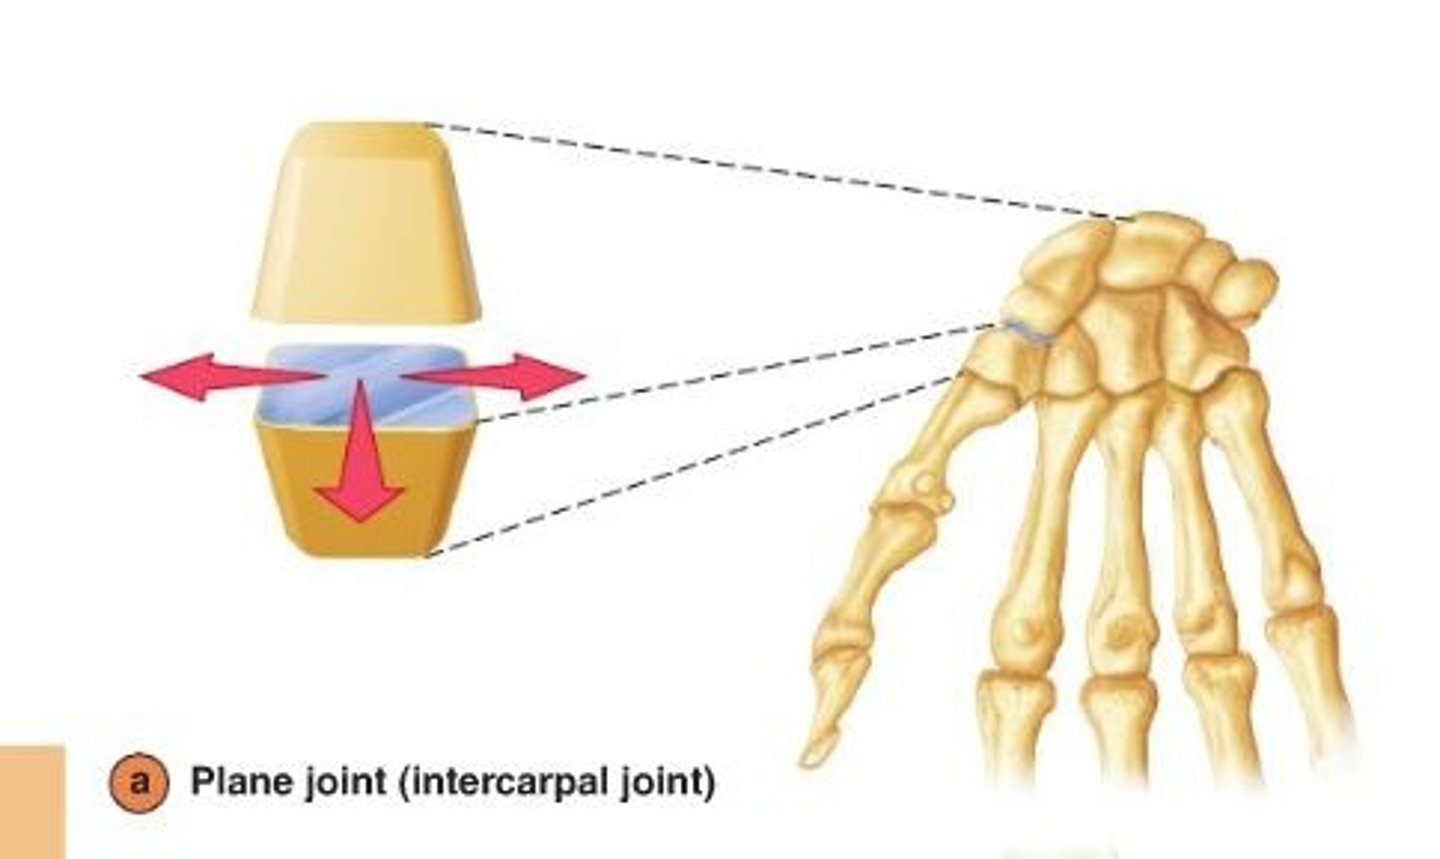

Plane synovial joint

allow sliding or gliding movements when one bone moves across the surface of another

ex: acromioclavicular joint